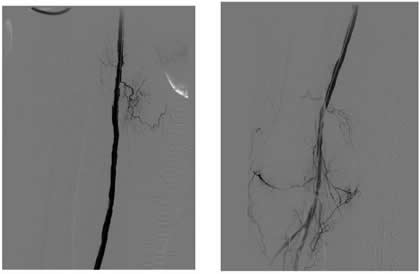

Case 2: A 74-year-old male with new onset severe claudication and threatened toes on the right side. An up-and-over wire was able to be advanced into the superficial femoral artery (but was totally occlusive). Cryoablation restored patency (Figure 2).

![]() |

| Figure 2 |